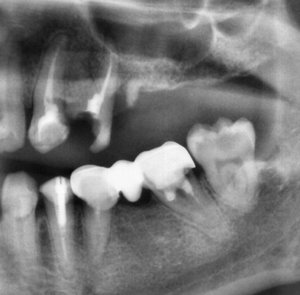

Отвалилась старая пломба, которую ставили девять лет назад. Пришел к стоматологу, она осмотрев сказала, что надо зачистить и заново запломбировать. Начав процедуру чистки, она попробовала пошатать зуб, потом сказала, что нужно сделать снимок. Снимок сделали, ее вердикт — надо удалять зуб, поскольку пошло воспаление вокруг корней, если его лечить со штифтами или еще как, через некоторое время он снова даст о себе знать и все равно придется удалить.

Смысл конечно всегда есть, но если диагноз доктора подтвердится (воспаление на корнях), то скорее всего зуб придётся удалить.